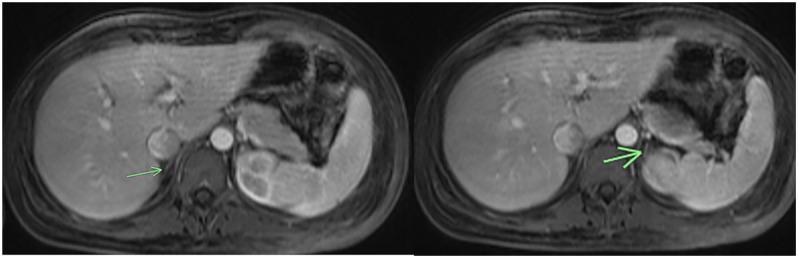

This case report highlights the initial presentation of Addison's disease in a 19-year-old individual with coronavirus disease. Coronavirus disease is an infectious disease, which often presents with fever and respiratory and gastrointestinal symptoms. Here, we describe a challenging case of a patient with coronavirus disease, who initially presented with altered mental status, hyponatremia, and cerebral edema, with subsequent workup leading to the diagnosis of Addison's disease.

本病例报告重点介绍了一名19岁冠状病毒病患者艾迪生病的初始表现。冠状病毒病是一种传染病,常表现为发热以及呼吸道和胃肠道症状。在此,我们描述了一例冠状病毒病患者的具有挑战性的病例,该患者最初表现为精神状态改变、低钠血症和脑水肿,随后的检查确诊为艾迪生病。